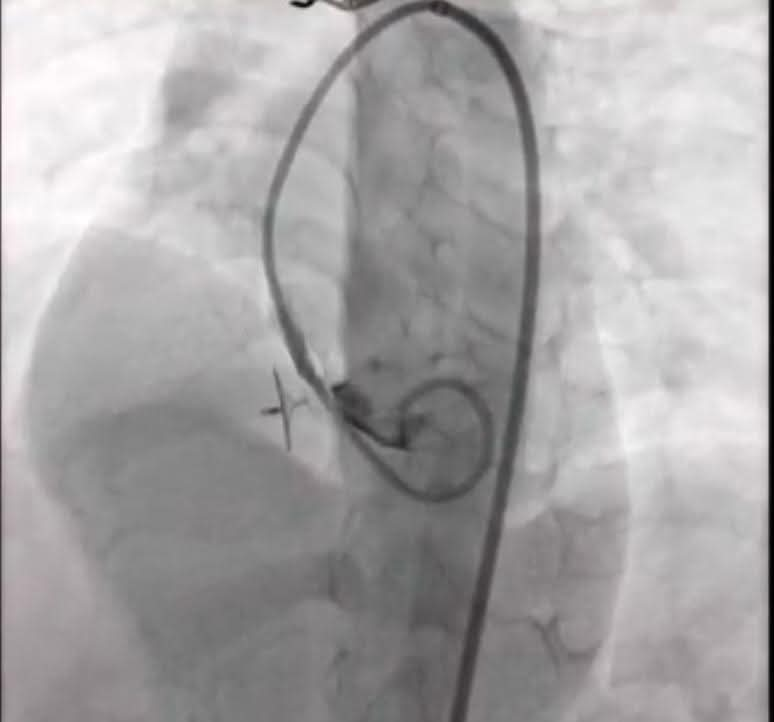

وتفاصيل الحالتين، الأولى حالة معقدة لطفل 5 سنوات من محافظة كفر الشيخ يعانى من تضخم بعضلة القلب نتيجة ثقب بين البطين وتم غلق الثقب بنجاح بينما الحالة الثانية حالة معقدة لطفل 16 سنة من محافظة الغربية تعانى من جلطة سابقة وتم غلق ثقب جنينى بين الأذينين، ويعد نجاح منقطع النظير وسط انبهار جميع الحاضرين من المصريين والأجانب بمختلف الجنسيات الذين شاهدوا أحداث البث الحي المباشر وكلا الحالتين ضمن جهود مستشفيات جامعـة طنطا لتنفيذ توجيهات القيادة السياسية في القضاء على قوائم الانتظار .